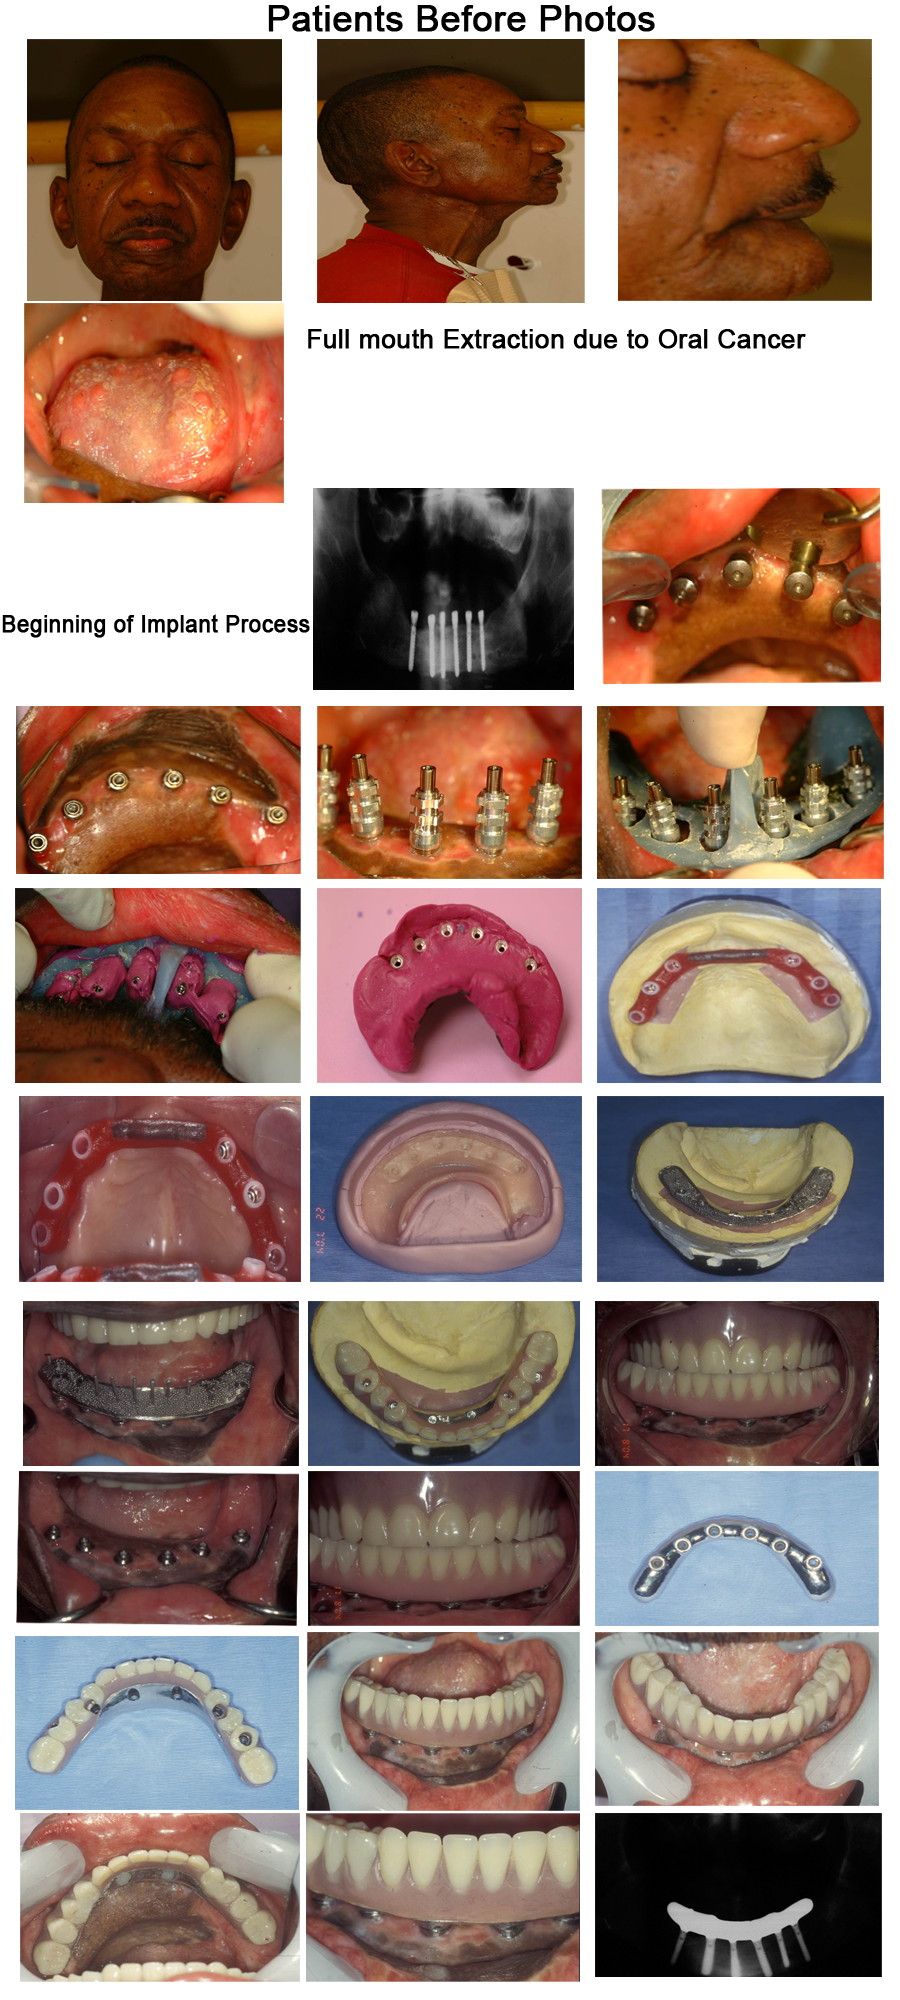

This case was a screw retained hybrid prothesis for a 58 year old male who survived oral cancer. Due to the oral cancer, this patient had lost half his tongue and had to have his teeth removed. The treatment plan presented to him was Screw Retained Implant Supported Fixed Complete Mandibular Dentures (Hybrid Denture) and a Complete Maxillary Denture. Below is the process completed.